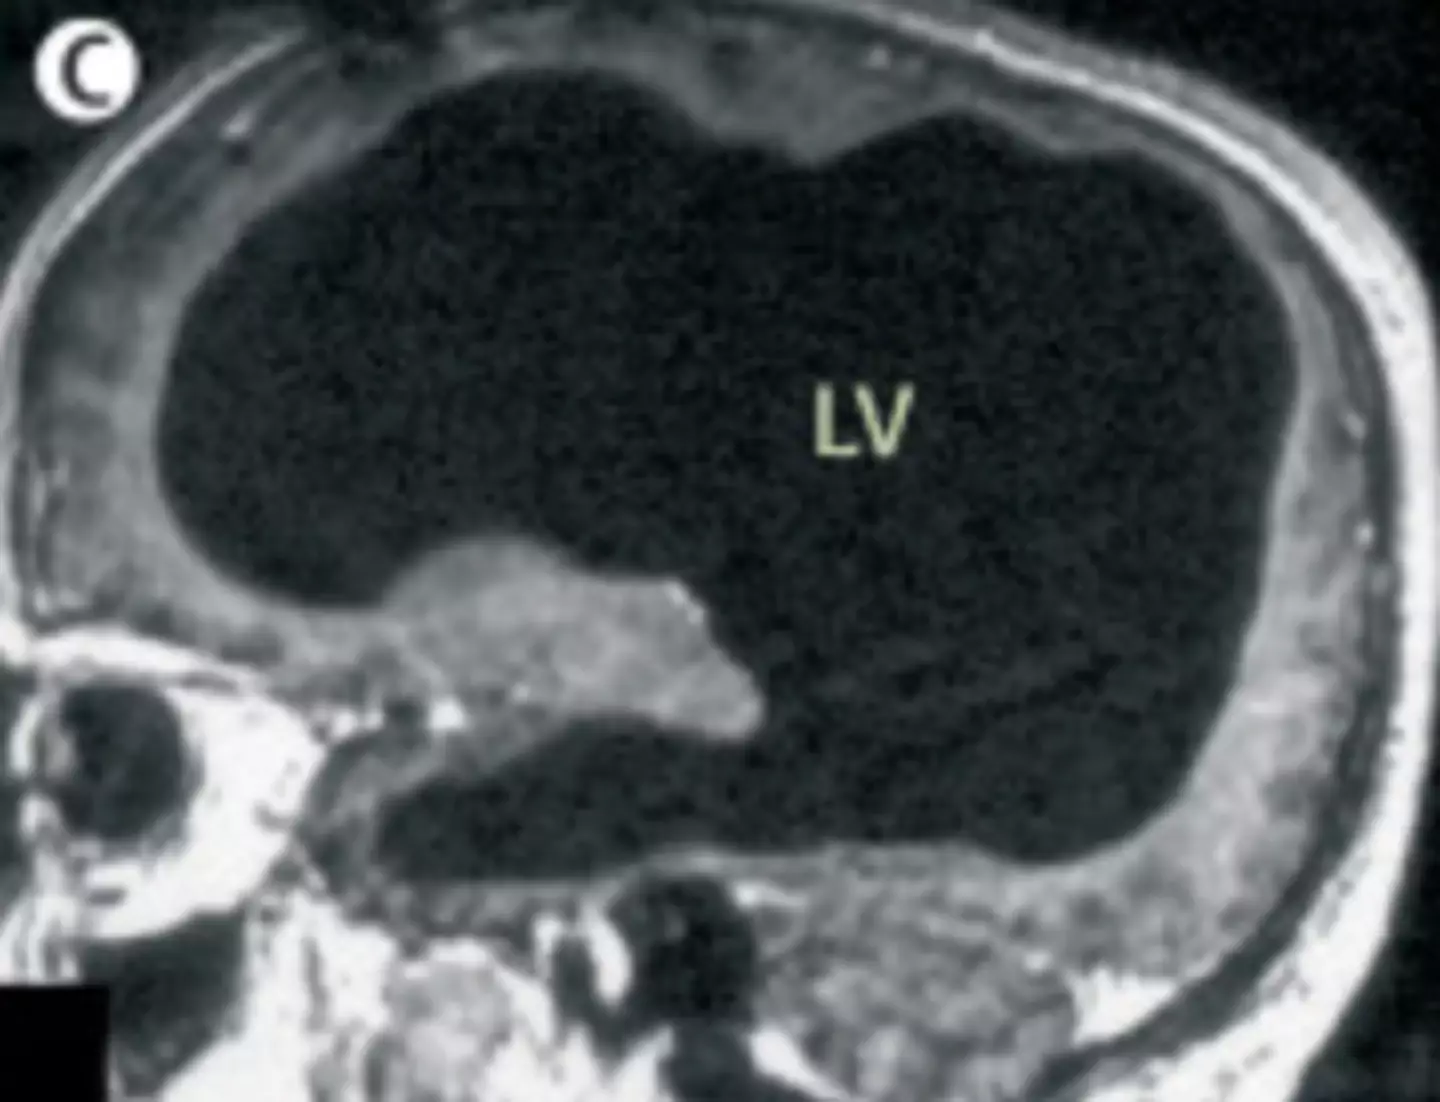

The doctors learned that the man had a condition called Hydrocephalus, a build-up of fluid in the brain; he actually had a shunt placed inside his head at just six years old to drain the fluid, but it was removed when he turned 14.

Speaking about the case, Feuillet confirmed that the fluid buildup had led to a significant reduction in brain matter: "It is hard for me [to say] exactly the percentage of reduction of the brain, since we did not use software to measure its volume. But visually, it is more than a 50 to 75 percent reduction.

"The whole brain was reduced – frontal, parietal, temporal, and occipital lobes – on both left and right sides. These regions control motion, sensibility, language, vision, audition, and emotional and cognitive functions," Feuillet went on to tell New Scientist.